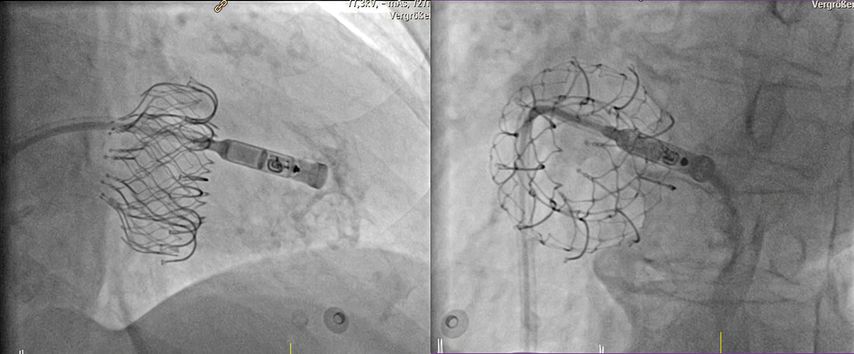

Abb. 4: Implantation eines sondenlosen Herzschrittmachers (Medtronic MicraTM) in den rechten Ventrikel bei vorbestehendem interventionellem Trikuspidalklappenersatz (EvoqueTM). Zur optimalen Positionierung wird über den Delivery-Katheter Kontrastmittel verabreicht. Die sondenlose Schrittmacherkapsel ist noch mit dem Delivery-Katheter verbunden. Links: Ansicht von schräg rechts vorne (RAO), rechts: Ansicht von schräg links vorne (LAO)

Seit einigen Jahren kann auch eine Schrittmacherkapsel in den Vorhof implantiert werden.13 Dies ermöglicht zusätzlich zur VVI/VDD-Stimulation nunmehr eine rein atriale bzw. eine DDD-Stimulation. Die sondenlose Herzschrittmachertherapie stellt somit für eine deutlich größere Bandbreite an zugrunde liegenden bradykarden Rhythmusstörungen eine therapeutische Option dar.